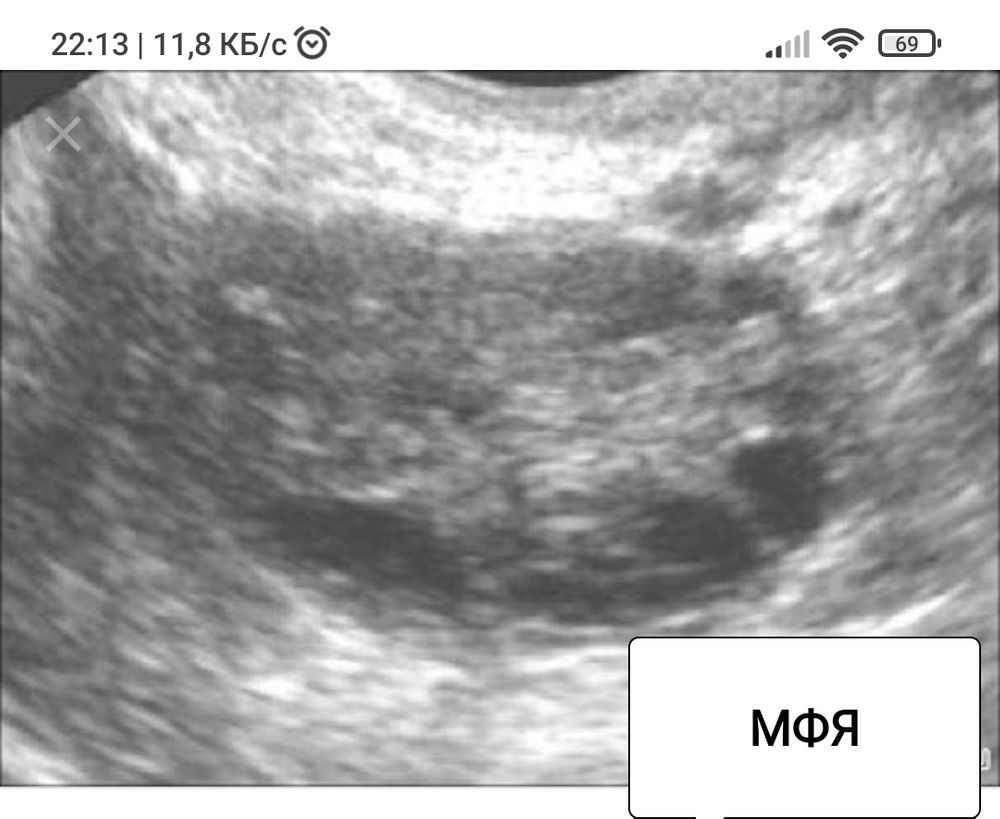

Немного покопавшись в интернете, я нашла четкое сравнение этих диагнозов. Но, что больше всего мне понравилось - сравнение УЗИ. Сопоставив все факты (фото приложу ниже) и своё УЗИ я наконец поняла - тут, кажется, ярко выраженные МФЯ. Не понимаю, зачем было только запугивать все это время тем что " с таким то диагнозом, попробуйте и родить... это будет чудо "🤦♀️🤷♀️

МФЯ - это просто количество антральных фолликулов >15-20.

Соответственно, если у Вас есть ановуляции/олигоовуляции и гиперандрогения, то картина УЗИ уже не важна. А если есть только множество фолликулов на УЗИ, то никакого СПКЯ у Вас нет.

У вас мфя, это нормальное состояние яичников для здоровой молодой женщины. Спкя это патология. Врачи часто путают это🤦♀️🤦♀️🤦♀️